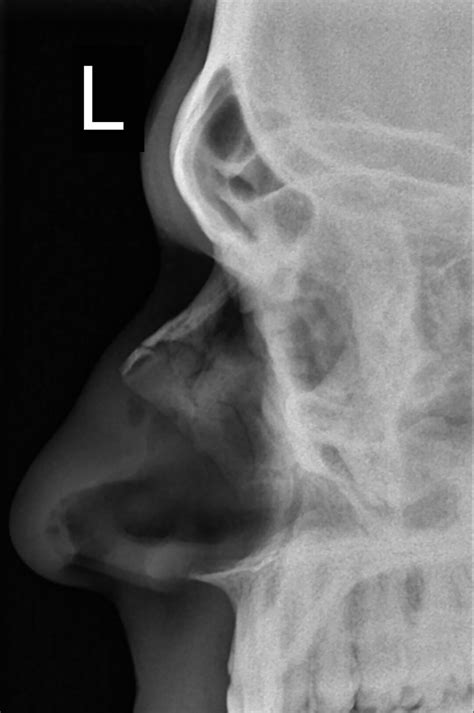

Imaging tests, such as X-rays or CT scans, may be ordered to confirm the diagnosis and determine the extent of the fracture. These tests can also help rule out other injuries, such as fractures of the facial bones or a skull fracture.

• broken nose x ray image